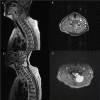

Intramuscular myxomas are rare, benign mesenchymal tumours, occurring predominantly in large skeletal muscles as large, slow-growing and painless masses. Spinal occurrence is rare, and may present incidentally, or diagnosed via localized symptoms secondary to local infiltration of surrounding structures. Differential diagnosis based on imaging includes sarcomas, meningiomas and lipomas. We discuss two contrasting cases presenting with well-circumscribed cystic paraspinal lesions indicative of an infiltrative tumour and discuss the radiological and histological differences that distinguish myxomas from similar tumours. Surgical resection of the tumour was performed in both cases, however one patient required surgical fixation due to bony erosion secondary to tumour infiltration. Immuno-histopathological analysis confirmed the diagnosis of a cellular myxoma. Follow up imaging at 6 months confirmed no symptomatic or tumour recurrence in both cases. Histological analysis is the definitive means for diagnosis to differentiate myxomas from other tumours. Recurrence is rare if full resection is achieved.